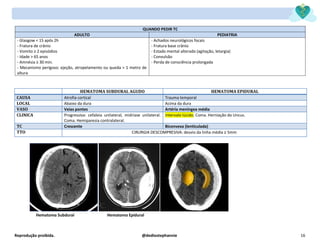

HEMATOMA SUBDURAL AGUDO HEMATOMA EPIDURAL

CAUSA Atrofia cortical Trauma temporal

LOCAL Abaixo da dura Acima da dura

VASO Veias pontes Artéria meníngea média

CLINICA Progressiva: cefaleia unilateral, midríase unilateral.

Coma. Hemiparesia contralateral.

Intervalo lúcido. Coma. Herniação do Uncus.

TC Crescente Biconvexa (lenticulada)

TTO CIRURGIA DESCOMPRESIVA: desvio da linha média ≥ 5mm

Hematoma Subdural Hematoma Epidural